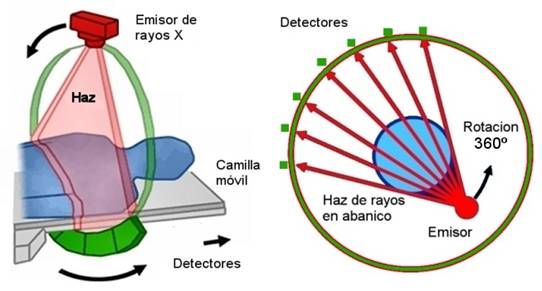

TERCERA GENERACIÓN 1976

• Rotación, Rotación

• 300-500 detectores

• Haz de RX cubre el ancho de la exploración

• Adquisición 2-10 Seg.

GANTRY

DETECTORES

TUBO DE RX